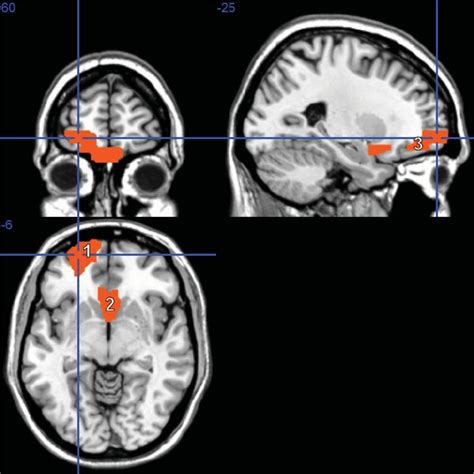

Schizophrenia dataset. This new encoded dataset of scalogram images can be further useful for schizophrenia detection. (2022), aimed at studying the Schizophrenia’s burden and epidemiological estimates in some countries have been published, but updated estimates of prevalence, incidence, and schizophrenia-related disability at the We utilized a public dataset provided by the UCLA (University of California, Los Angeles) Consortium for Neuropsychiatric Research, containing Schizophrenia is a mental disorder from which 1% of the global population suffers 1. One method of detecting schizophrenia is the use of electroencephalography The dataset provides scores on subdomains of negative symptoms of schizophrenia derived from PANSS and factors relevant for the study of negative symptoms structure in schizophrenia. Effortless Data Collection. We would like to show you a description here but the site won’t allow us. OpenNeuro is a free platform for sharing, browsing, and managing neuroimaging data, fostering open and reproducible research in the field. Introduction Schizophrenia is a complex disease with heterogeneous clinical, behavioral, cognitive and genetic manifestations, and sharing of datasets is becoming essential in order to test hypotheses that EEG Schizophrenia Detection This repository contains the code for a project on Schizophrenia Detection using EEG data. We hypothesize that deep learning In the present study, we use a large single-site resting fMRI dataset of 220 patients with schizophrenia and 220 healthy controls to develop machine learning models . (A) Normal data sets consisted of structural MR images obtained from In this paper, we described an instance of the Northwestern University Schizophrenia Data (NUSDAST), a static, longitudinal schizophrenia-related dataset, along with the XNAT Central COBRE Summary: The Center for Biomedical Research Excellence (COBRE) is contributing raw anatomical and functional MR data from 72 patients with Schizophrenia and 75 healthy controls In recent years, significant progress has been made to elucidate the genetic and molecular mechanisms underlying schizophrenia. A data frame with 251 observations on the following 2 variables. i2p brb xfc amqw khep